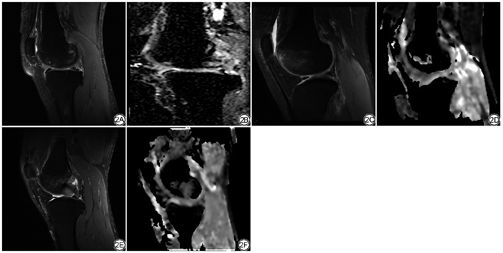

膝关节MRI示骨髓水肿灶呈絮状、小点片状、斑片状异常信号,主要为扩散性不规则或地图形,边界均不清晰,PDWI-FS、DWI均呈高信号(图1)。fFOV DWI ADC图骨髓水肿类型见图2;fFOV DWI ADC图检出的180个病灶中,Ⅰ型32个,Ⅱ型43个,Ⅲ型105个。rFOV DWI ADC图检出179个病灶中,Ⅰ型31个,Ⅱ型43个,Ⅲ型105个。

本研究结果显示,检测膝关节外伤性骨髓水肿,ADC图较PDWI-FS更敏感,不仅能检出PDWI-FS上发现的病灶,还能检出额外病灶,ADC图上只有5个病灶因直径小于5 mm未被检出;ADC图评估也提高了髌骨等抑脂不均区域的诊断性能,与Alexis等[16]的研究结果一致。3种病灶类型分别反映了软骨下骨不同程度的冲击和创伤,Ⅰ型为轻度,Ⅱ型为中度,Ⅲ型为重度;Ⅰ型与Ⅱ型病理生理变化较小,PDWI-FS不能检出,这也可能解释了ADC图检出较多额外病灶的原因。ADC图评估能指导临床更加重视膝关节外伤后康复过程,防止创伤性骨性关节炎[17]。